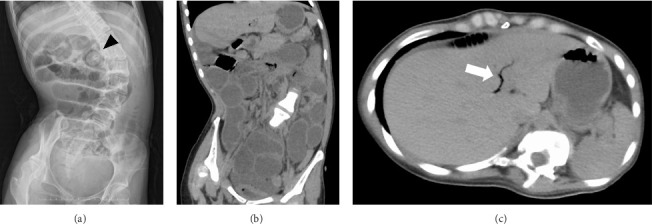

Gallstone ileus is an uncommon complication of cholelithiasis and the delayed diagnosis may be associated with increased risk of mortality. When gallstones block the cystic duct, they can lead to cholecystitis. If a fistula forms between the inflamed gallbladder and the adjacent intestine, the gallstones may pass into the intestinal tract and cause obstruction in the intestine. We report a case of 25-year-old female with developmental and epileptic encephalopathy who was intraoperatively diagnosed with gallstone ileus during surgery for small bowel obstruction of unknown origin. The patient had potential risk factors enhancing the formation of cholesterol gallstones, including long-term use of phenobarbital, vagus nerve injury in open gastrostomy and laparoscopic fundoplication, and tube feeding; however, the patient's gallstone had been undiagnosed for a long time. Computed tomography of the abdomen showed small bowel obstruction and pneumobilia. The presence of pneumobilia in a patient without a surgical history of the biliary system should raise suspicion of a bilioenteric fistula. The awareness of this complication of cholelithiasis is important to make an early diagnosis and to initiate the appropriate treatment.

Abstract Image